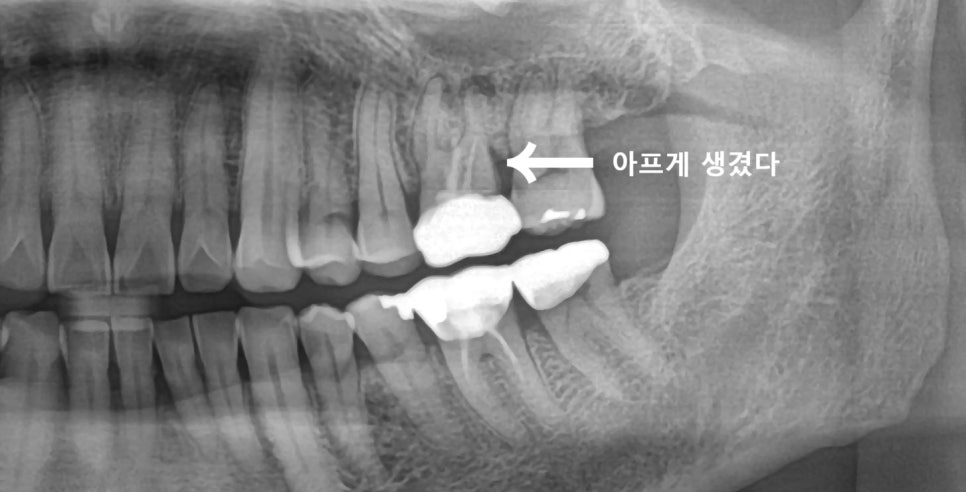

엑스레이 사진을 찍어보니,

옛날에 신경치료 받으시고

금니까지 씌워놓은 치아인데..

크라운을 뜯고 엑스레이를 찍는데

뿌리 끝에 염증이 가득하다.